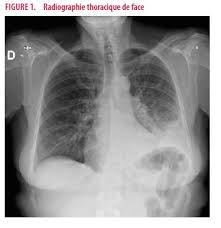

Trinkwasserhygiene Und Installation Beuth De from www.beuth.de L'évaluation et la prise en charge de la douleur constituent un véritable enjeu de santé publique en tant que critère de qualité. Autres examens réalisables (consensus 2006) : Les indicateurs sanitaires indiquent une nette reprise très rapide de l'épidémie dans notre région liée à la circulation accrue du variant delta. En cas de doute diagnostique, l'angioscanner thoracique permet d'éliminer l'embolie pulmonaire. Adnopathies médiastinales (hyperplasie lymphoide) et splénomégalie • examen médullaire normaux • 433 lc cd4+, absence de cellules b mémoires switchées, cd45ro 91,2% • pas d'anticorps pour les sérologies virales testées et vaccinales • instauration d'une substitution par ig iv puis sc au long cours. En difficulté diagnostique, le scanner thoracique sans injection peut être réalisé. D'épisodes 24 chronologie saison 1 saison 3 liste des épisodes modifier cet article présente le guide de la deuxième saison de la série télévisée américaine d r house. Jan 13, 2021 · une épidémie de pneumonies, décrite à l'époque comme d'allure virale de cause inconnue a émergé dans la ville de wuhan (province de hubei, chine) en décembre 2019.

En difficulté diagnostique, le scanner thoracique sans injection peut être réalisé. Le 9 janvier 2020, la découverte d'un nouveau coronavirus a été annoncée officiellement par les autorités sanitaires chinoises et l'organisation mondiale de la santé (oms). Les indicateurs sanitaires indiquent une nette reprise très rapide de l'épidémie dans notre région liée à la circulation accrue du variant delta. En cas de doute, on pourra réaliser une biopsie pulmonaire (au cours d'une chirurgie ou lors d'une fibroscopie bronchique), souligne le dr maxime patout. Autres examens réalisables (consensus 2006) : Jul 02, 2020 · une embolie pulmonaire est due à l'obstruction d'une artère pulmonaire par un caillot de sang. Adnopathies médiastinales (hyperplasie lymphoide) et splénomégalie • examen médullaire normaux • 433 lc cd4+, absence de cellules b mémoires switchées, cd45ro 91,2% • pas d'anticorps pour les sérologies virales testées et vaccinales • instauration d'une substitution par ig iv puis sc au long cours. Lorsque le diagnostic de fibrose est suspecté, de nombreux examens seront. La loi relative aux droits des malades et à la qualité du système de santé du 4 mars 2002 reconnaît le soulagement de la douleur comme un droit fondamental de toute personne. L'évaluation et la prise en charge de la douleur constituent un véritable enjeu de santé publique en tant que critère de qualité. Le caillot se fixe dans 9 cas sur 10 préalablement sur la paroi d'une veine profonde de l'abdomen, du bassin ou d'un membre inférieur, migre dans le sang et s'arrête dans une artère pulmonaire. Antigène urinaire du streptoccocus pneumoniae. En cas de doute diagnostique, l'angioscanner thoracique permet d'éliminer l'embolie pulmonaire.

Merkblatt Legionellen Prophylaxe Und Beprobung Pdf Kostenfreier Download from docplayer.org En cas de doute diagnostique, l'angioscanner thoracique permet d'éliminer l'embolie pulmonaire. Adnopathies médiastinales (hyperplasie lymphoide) et splénomégalie • examen médullaire normaux • 433 lc cd4+, absence de cellules b mémoires switchées, cd45ro 91,2% • pas d'anticorps pour les sérologies virales testées et vaccinales • instauration d'une substitution par ig iv puis sc au long cours. Le 9 janvier 2020, la découverte d'un nouveau coronavirus a été annoncée officiellement par les autorités sanitaires chinoises et l'organisation mondiale de la santé (oms). Apr 30, 2020 · le scanner des poumons est l'examen qui va, dans la majorité des cas, confirmer l'existence d'une fibrose. Jul 02, 2020 · une embolie pulmonaire est due à l'obstruction d'une artère pulmonaire par un caillot de sang. Antigène urinaire du streptoccocus pneumoniae. Le caillot se fixe dans 9 cas sur 10 préalablement sur la paroi d'une veine profonde de l'abdomen, du bassin ou d'un membre inférieur, migre dans le sang et s'arrête dans une artère pulmonaire. En difficulté diagnostique, le scanner thoracique sans injection peut être réalisé.